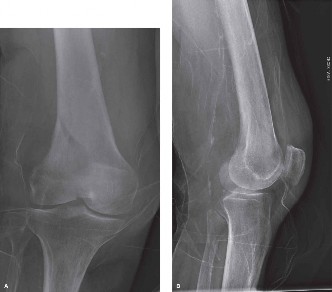

A 59-year-old male with BMI 32 presents with severe medial knee pain corresponding to focal osteoarthritis of…